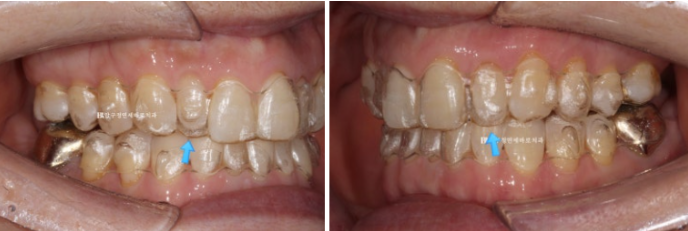

The patient wanted orthodontic treatment because the two front teeth were lowered and the teeth were spaced apart.

23.09

This patient is in their late 50s and works as a senior model.

Because the two front teeth were significantly lowered, the overbite was severe.

When there is an overbite, every time you bite down, the lower front teeth push the upper front teeth from back to front, causing the space between the upper front teeth to gradually widen and the teeth to protrude forward.

The blue arrow indicates a peg lateral tooth.

On one side, resin had been attached temporarily to fill the gap.

Since orthodontic treatment was planned, the resin used to fill the space was removed, and a scan was taken to make the appliance.

The lower teeth were also crooked.

Originally, after orthodontic treatment, only the peg lateral tooth was to have its size restored with veneers, but later it was decided to place no-prep laminate veneers on all eight front teeth.

There is also wire braces, but since the patient is a model, I recommended Invisalign Lite, a clear aligner, so it would not interfere with daily life.